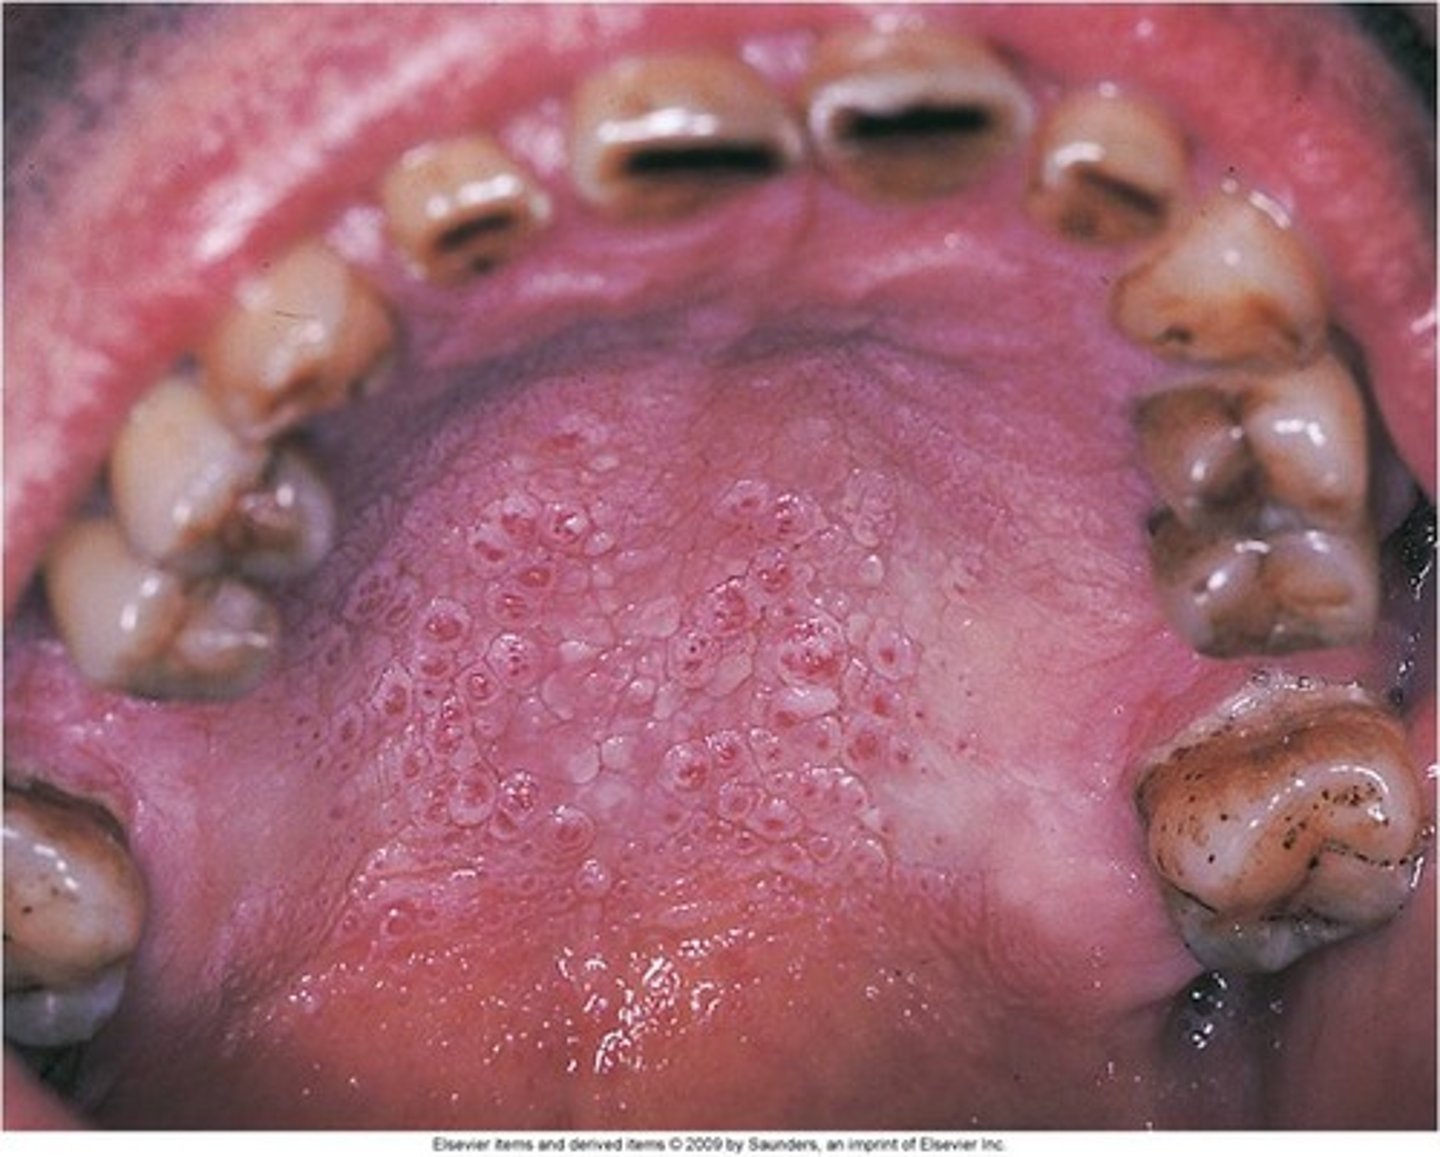

Name the pathology: picture of palate with numerous small raised areas with central red dots caused by pipe smoking

This is not premalignant and is caused by the ____ form the smoke. Not the chemicals

tx?

nicotonic stomatitis

heat from the smoke, not the chemicals

is reversible, need to stop smoking

Name the pathology: can be seen on the palate in a pipe smoker

nicotonic stomatitis